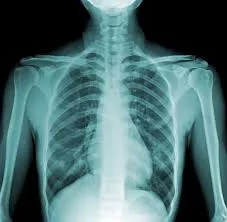

Фото: FoodandHealth

Специалисты, которые отдали родному предприятию 30 и более лет, заработали неизлечимые болезни легких. Многим из них теперь очень сложно дышать, и чтобы хоть как-то иметь возможность жить, они вынуждены переезжать за город, где воздух гораздо чище, а также посоянно использовать лекарства.

- Около 30 лет в среднем составил стаж работы каждого во вредных и опасных условиях на ЧЭМК, в том числе в плавильных цехах, цехе обжига электродов и цехе графитации электродов, - комментирует правозащитный центр «Металлург». - В результате регулярного контакта с вредными веществами и воздействия вредных факторов (запыленность, тепловое излучение, промышленные аэрозоли и другие) им были установлены различные степени утраты трудоспособности, группы инвалидности и профессиональные заболевания — силикоз, антракоз и другие.